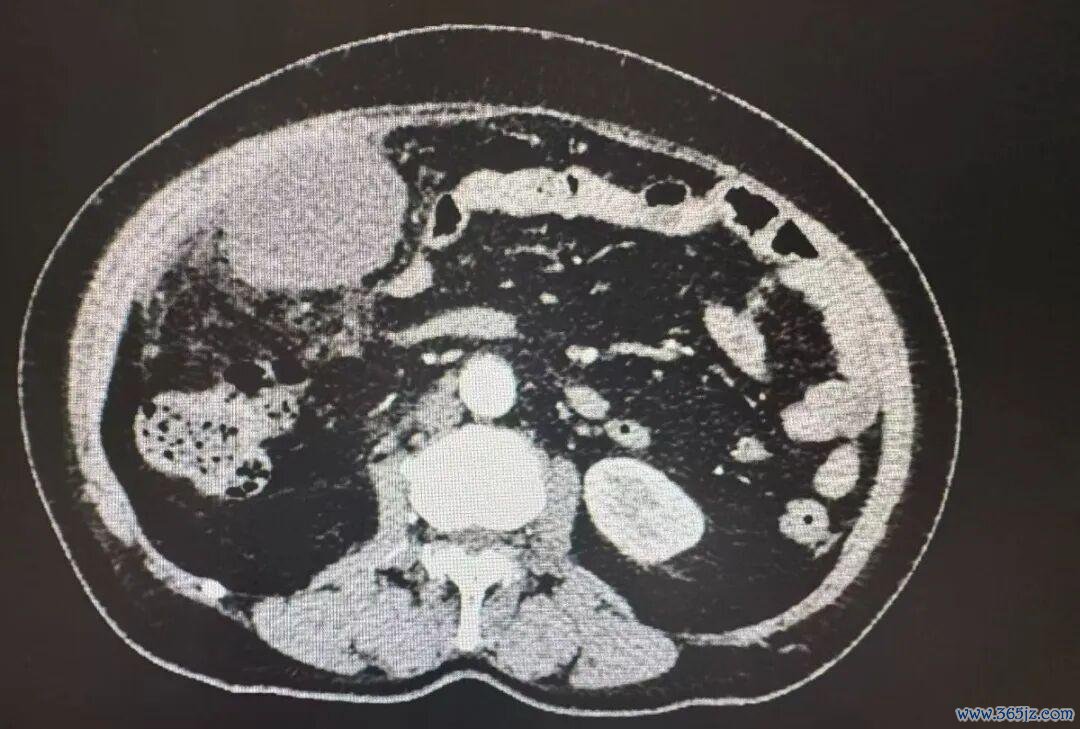

急诊查验遵守深刻,白细胞数值是遍及值的近四倍,CT示右下腹一团糟,阑尾不仅化脓穿孔,还变成了一个大脓肿,脓液依然扩散到悉数腹腔,医师推敲急性坏疽性阑尾炎伴穿孔,满盈性腹膜炎,阑尾周围脓肿。

与家属充分调换明,急诊腹腔镜微创手术火速进行。术中风光印证了术前的判断,当镜头探入腹腔,腹腔内里积了不少黄褐色脓液,肠子、子宫、大网膜等因为严重的炎症粘在沿途。

普外科手术团队副主任医师宋书亚、医师杨慧斌就像在纵横交叉的雷区里功课,提神翼翼地分手粘连的组织,最终在右侧腹腔的不同位置,找到了三个荫藏的脓肿,先后抽出了500毫升的脓液和坏死组织。